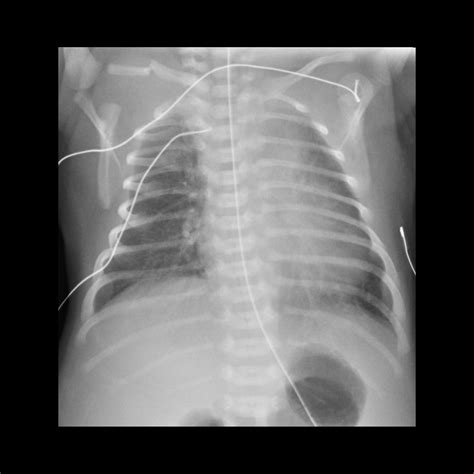

Diagnosing a broken collarbone in a newborn involves a physical examination and imaging tests. The healthcare provider will:

• Examine the baby's collarbone area for swelling, tenderness, and deformity

• Order an X-ray to confirm the fracture and assess its severity

In some cases, additional imaging tests such as an ultrasound or CT scan may be recommended to get a more detailed view of the injury.